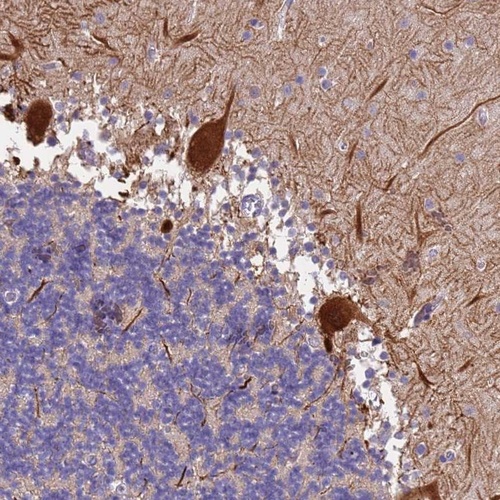

Immunohistochemical staining of human cerebellum shows strong cytoplasmic and nuclear staining in Purkinje cells.